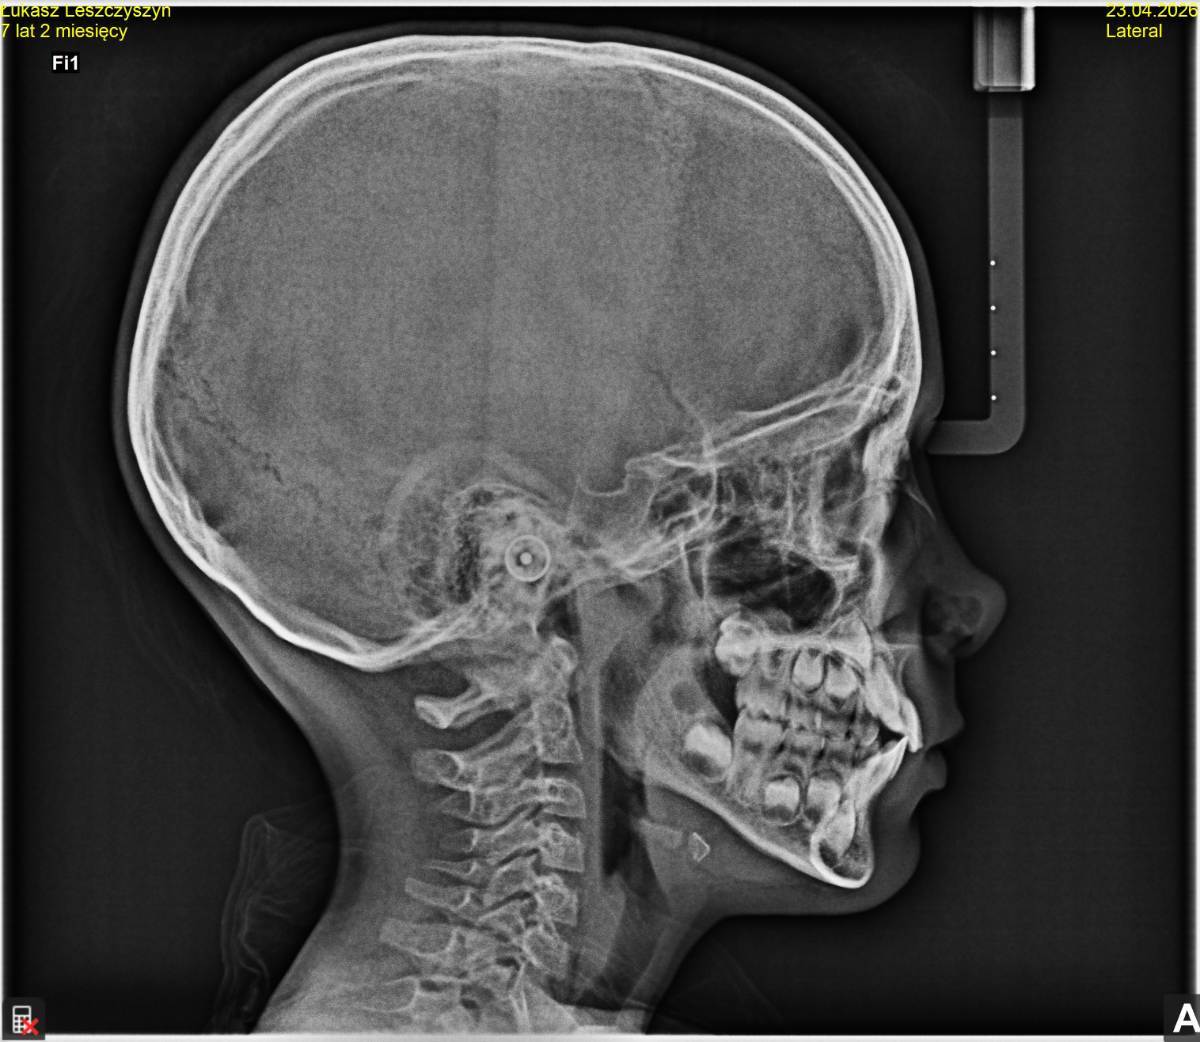

Ребенок 7 лет. Визуально - передний зуб выступает немного вперед. Между передними зубами пробел. Хотелось бы чтобы пробела не было.

Вот были у ортодонта. Все, что он сказал - записаться к нему на коррекцию 3х уздечек. Лазером. Он видит в этом главную проблему. И работать с логопедом. Но с логопедом работаем.  Еще что-то вспоминал про то, что у ребенка плохо развивается челюсть. Это как-то видно по рентгене?

Я читал, что если такие дела с передними зубами, то нужно ставить пластинку. Да? Возможно, после этого он хотел делать пластинку?

Или пойти к другому ортопеду... Еще увидел, что на рентгене возле носа с одной стороны темнее, а с другой светлее

Кстати, вот рентген черепа старшего сына.